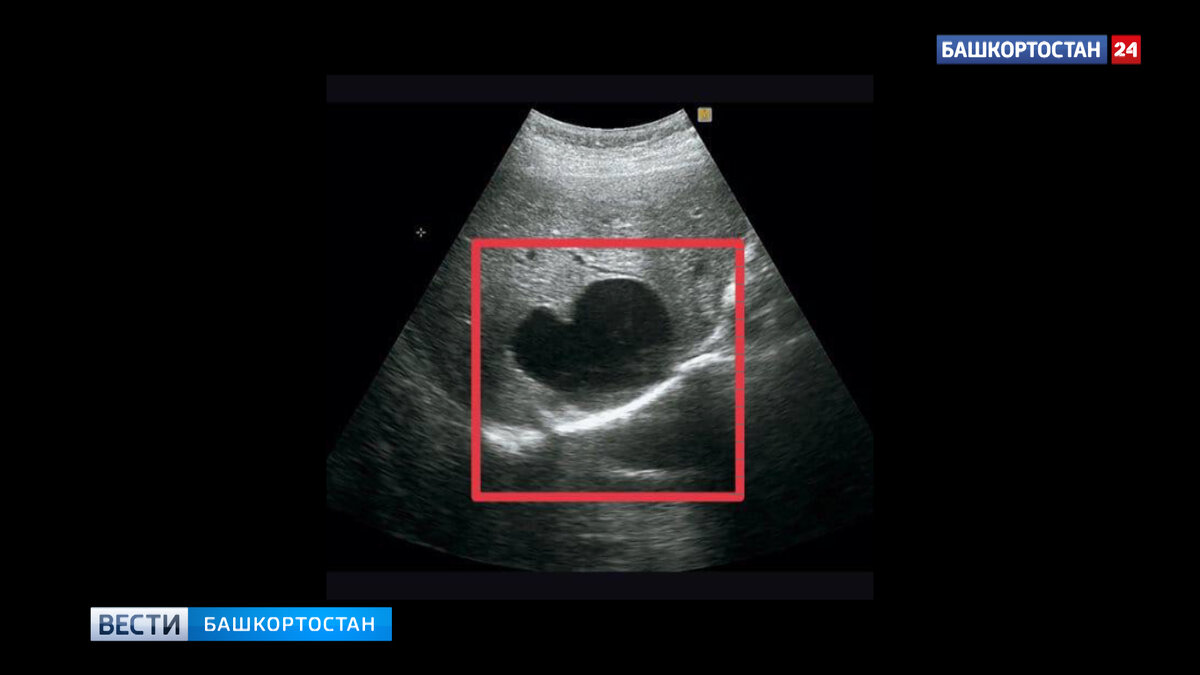

Ленточный червь образовал в печени жительницы Башкирии пузырь с паразитами. Он увеличивался в размерах и мог лопнуть, тогда паразиты проникли бы в кровеносную систему и полностью отравили организм. Однако, этого не случилось, благодаря своевременно оказанной врачебной помощи.

"Во время работы врачебного десанта в деревне Кинья-Абыз, специалист ультразвуковой диагностики городской больницы Кумертау Ирина Сычева проводила плановый осмотр пациентов. Во время исследования у одной из женщин была обнаружена киста в печени размером 70х50 мм. Врач заподозрила эхинококкоз и направила пациентку на дообследование, где диагноз подтвердился", — рассказал министр.

Известно, что эхинококкоз протекает довольно медленно. От момента заражения до первых проявлений заболевания может пройти несколько месяцев или даже лет. Поэтому большинство пациентов своевременно не обращаются к врачу — они просто не знают, что в их печени поселился паразит. Своевременное обследование помогло избежать печальных последствий. Ведь киста постепенно разрастается, что приводит к сдавливанию тканей, а это может спровоцировать разрыв. Когда это происходит, паразит оказывается в кровеносной системе и распространяется по всем органам и тканям.